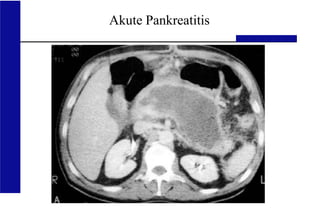

Akute Pankreatitis

normales Pankreas akute nekrotisierende

Pankreatitis

normales Pankreas akute Pankreatitis